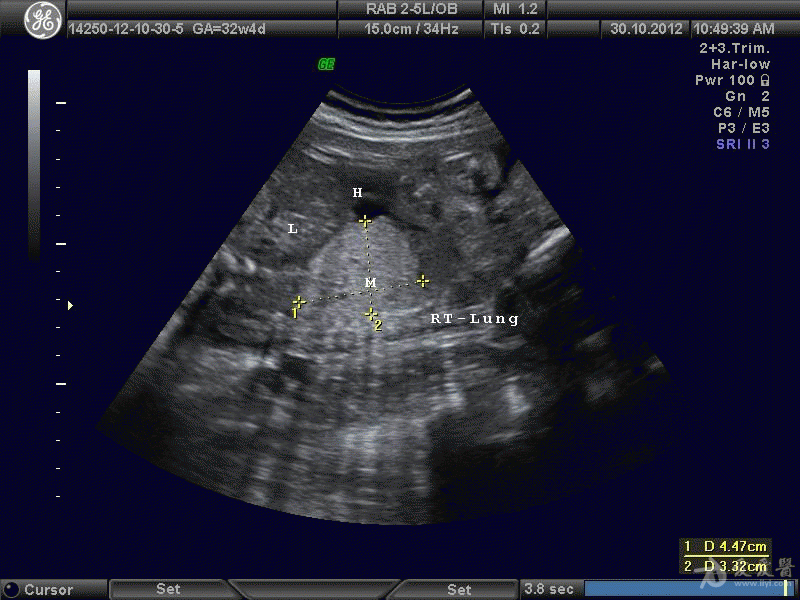

胎儿隔离肺图像共赏 - 超声医学讨论版 - 爱爱医医学论坛

图片尺寸800x600